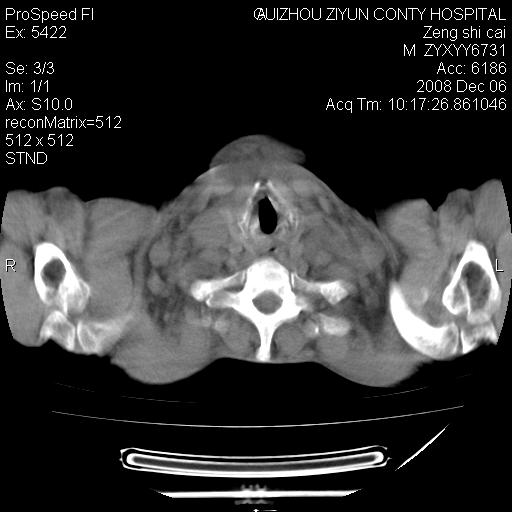

标题: CT16961:M、71岁,咳嗽半年,无血痰;胸片示右肺占位。 [打印本页]

标题: CT16961:M、71岁,咳嗽半年,无血痰;胸片示右肺占位。

右肺癌并纵隔淋巴结及胸膜转移可能性大

右肺癌并纵隔淋巴结及胸膜转移。建议气管镜

右肺纵隔型肺癌伴纵隔淋巴结及胸膜转移!

右肺纵隔型肺癌伴纵隔淋巴结转移!双侧胸水!

1)考虑右肺上叶纵隔型肺癌伴纵隔淋巴结转移。2)心包积液,双侧胸腔积液。

右肺癌并纵隔淋巴转移,腹膜后转移可能性大,两侧胸腔积液

右肺上叶纵隔型肺癌伴纵隔淋巴结转移。心包积液,双侧胸腔积液。

建议强化!主要鉴别是淋巴瘤与肺癌淋巴结转移。